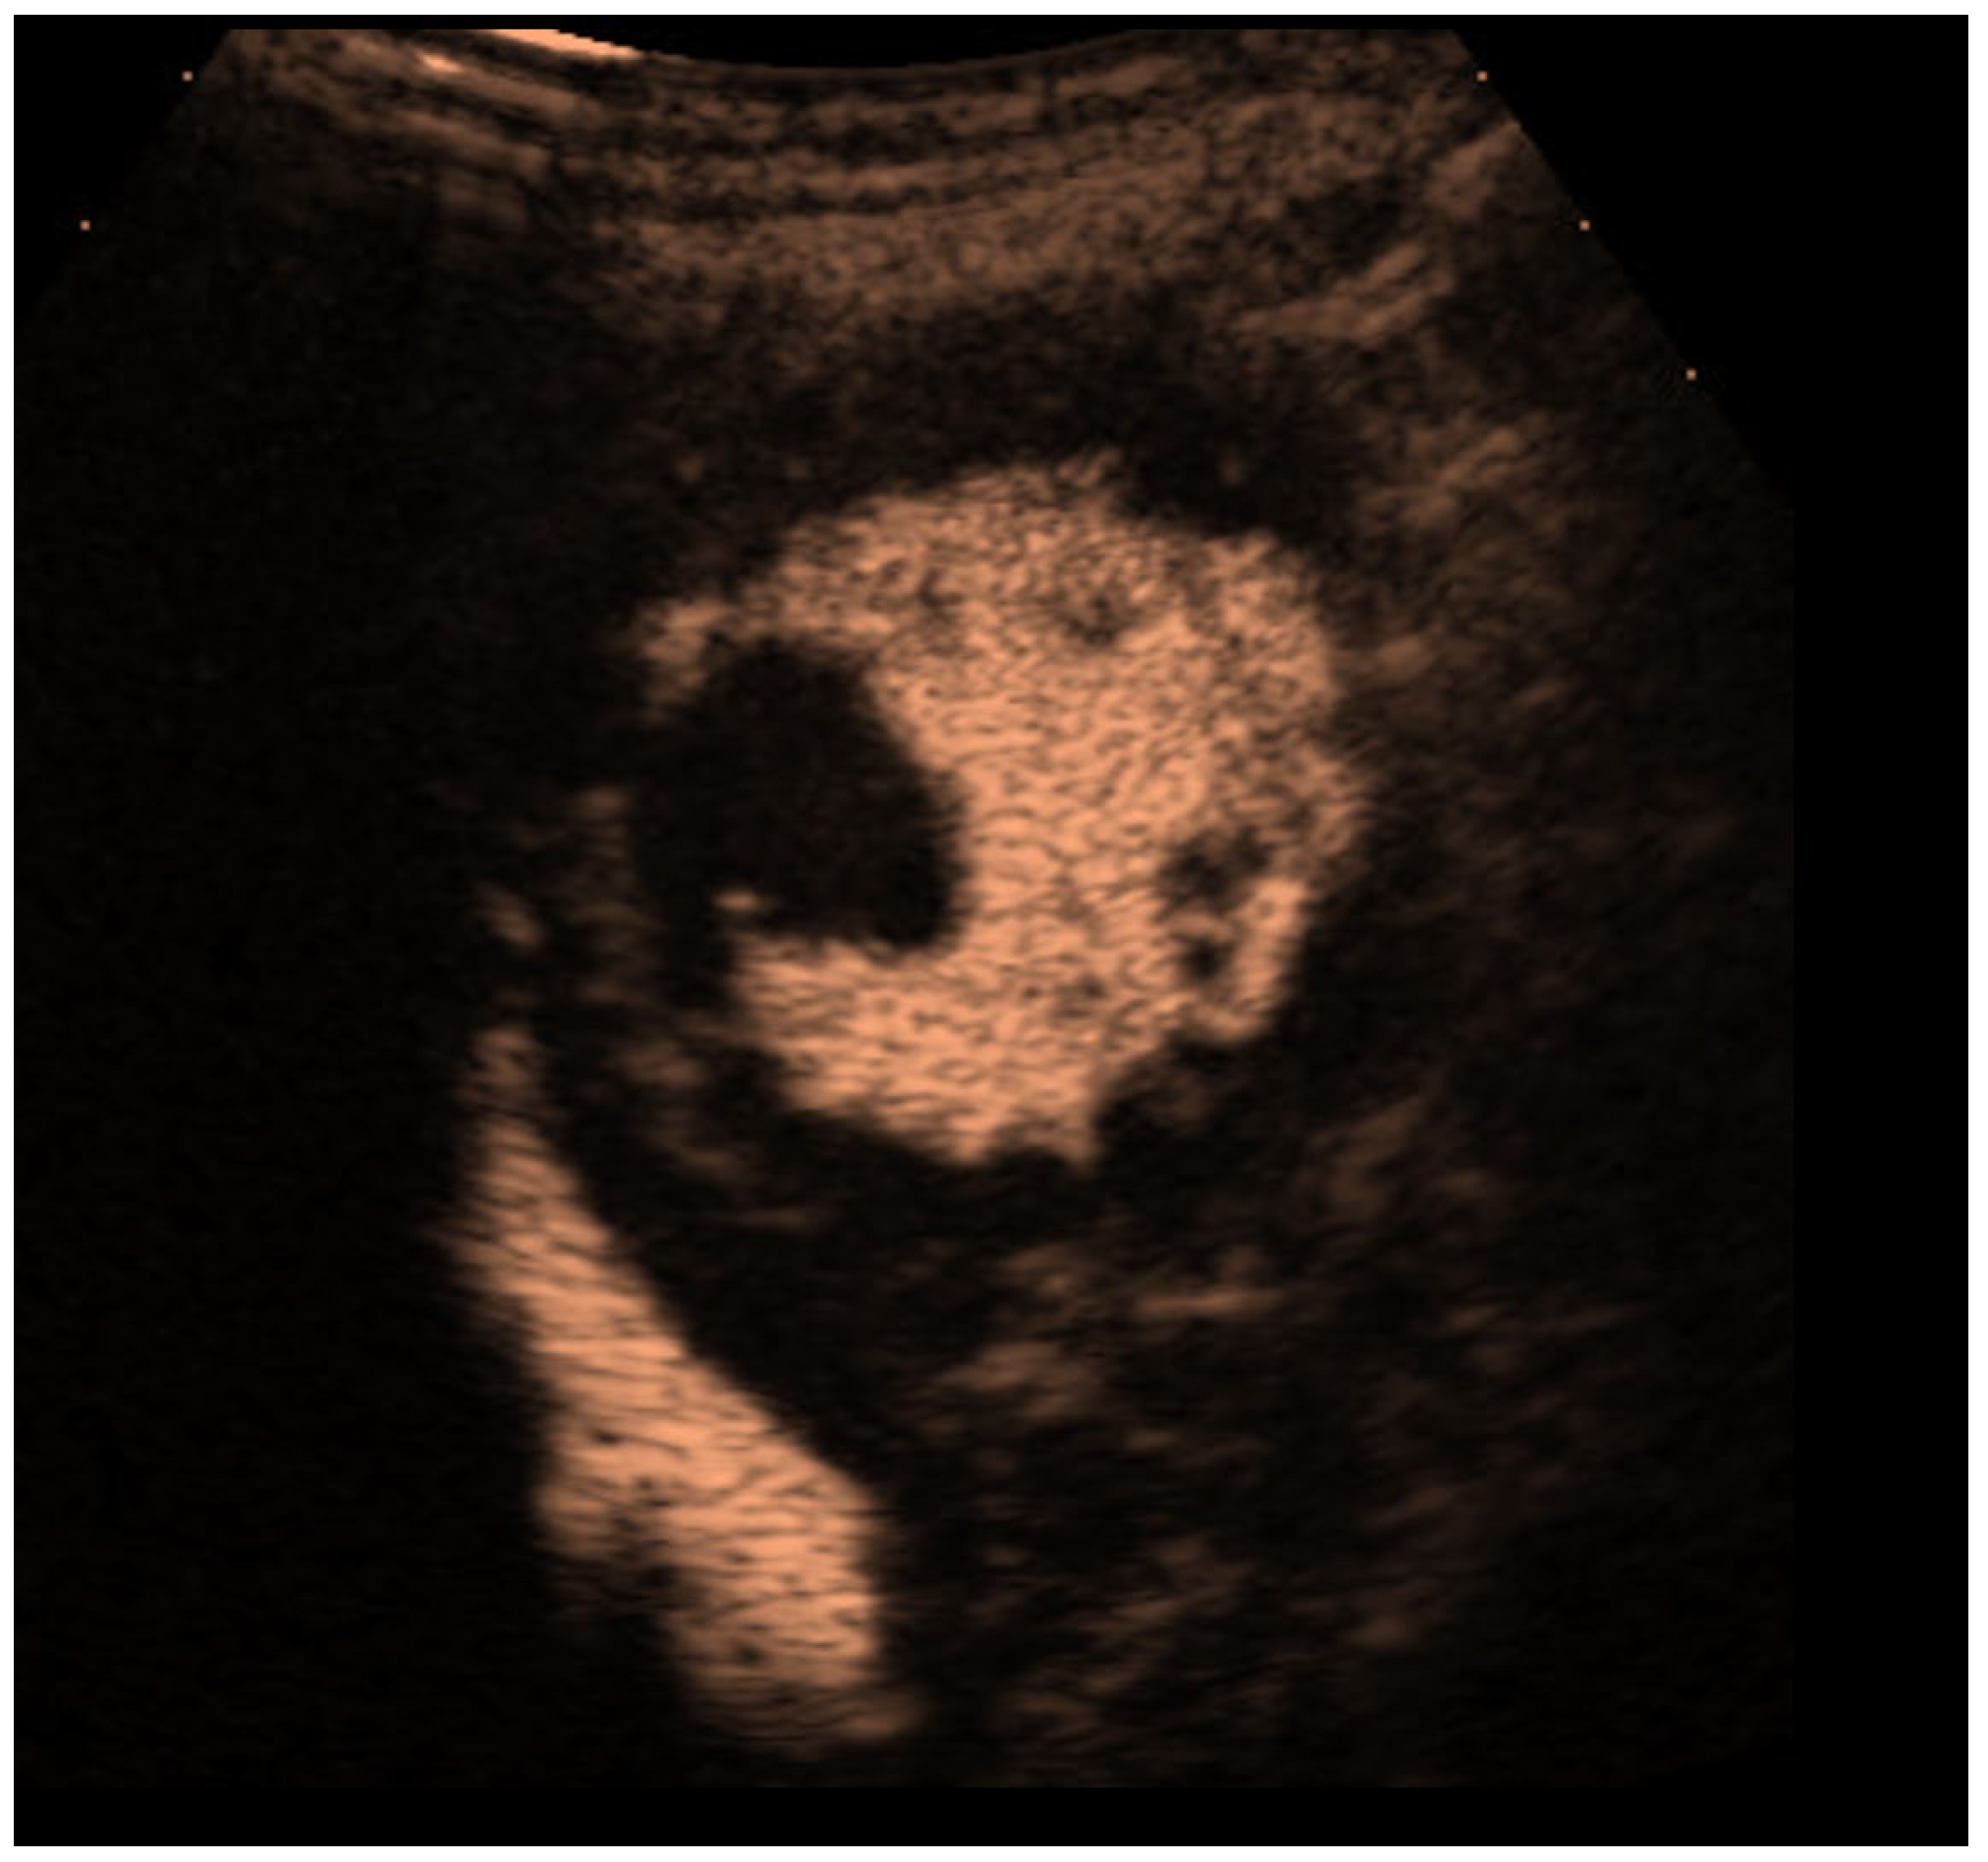

| Thrombi |

| Typical findings | 1. echofree mass 2. present in two different imaging planes 3. lump or laminar shape different from trabeculations’ documented size (two orthogonal diameters in at least one of the views), location, type (laminar vs. lump, single vs. multiple), surface (smooth vs. irregular) and mobility |